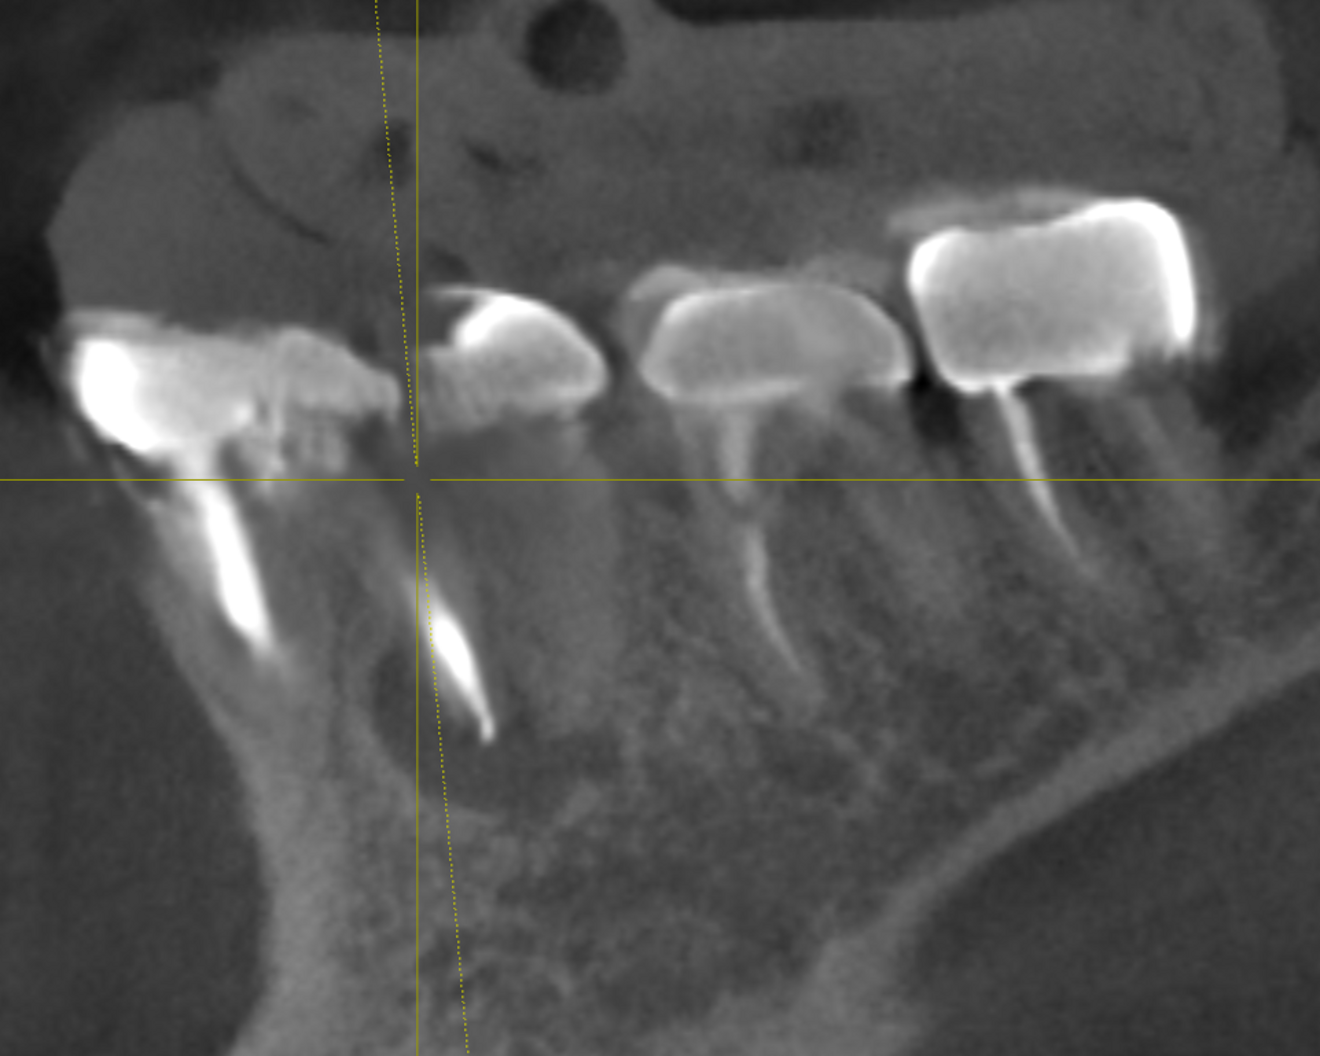

Figs. 2a–c: CBCT scan showing the failing endodontically treated tooth with an abscess.

The patient presented with multiple periapical radiolucencies associated with failing endodontically treated teeth, a horizontal root fracture and a failing long-span bridge (Fig. 1). A poor long-term prognosis was given to all the remaining mandibular teeth except tooth #46 (Fig. 2), and the treatment options, limitations and risks were reviewed thoroughly with the patient. The patient did not want a removable restoration and did not want to go a day without teeth and wanted to have biologically friendly materials used for treatment. It was decided to perform an immediate implant surgery and provide the patient with a stable temporary restoration to protect the healing implants for long-term success.